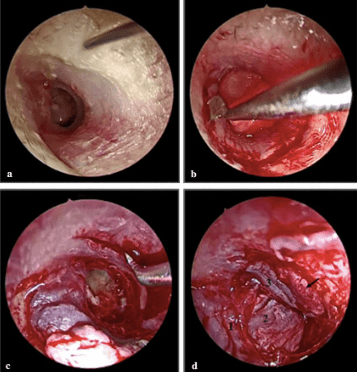

Endoscopic tympanoplasty (ET) provides minimally invasive transcanal access to the middle ear and improves middle ear visibility for the treatment of tympanic membrane (TM) perforations. However, the literature on surgical outcomes for large TM perforations is lacking and limited to small series. This study aimed to evaluate the clinical benefits of ET for large TM perforations.

This retrospective cohort study was conducted at nine tertiary referral hospitals in South Korea, where 252 patients who underwent ET as primary surgery from September 2019 to August 2021 were included. The outcome measures included the graft success rate and pre- and postoperative audiometric data.

In 239 patients, the graft success rate of ET for large or subtotal perforations was 86.2% (206 patients), while the graft failure rate was 13.8% (33 patients). The graft failure rate was directly correlated with surgical techniques, including overlay and medial or lateral underlay tympanoplasty (P=0.027). Lateral underlay tympanoplasty showed the most favorable results. Sex, laterality, etiology, site and size of perforation, operation time, and graft materials did not vary significantly between the graft success and failure groups (P>0.05). The mean air-bone gap (ABG) improved significantly in both groups (graft success group: 10.0±0.6 dB and graft failure group: 7.7±0.3 dB; P<0.001). However, the ABG improvement did not significantly differ between the groups. Analysis of covariance revealed that the postoperative 500-Hz bone conduction threshold improved after successful ET (adjusted coefficient, –11.351; 95% confidence interval, –21.491 to –1.212; P=0.028).

This study involved the largest population to date of large TM perforations treated by ET. The study findings suggest that ET is feasible and effective in treating large TM perforations.